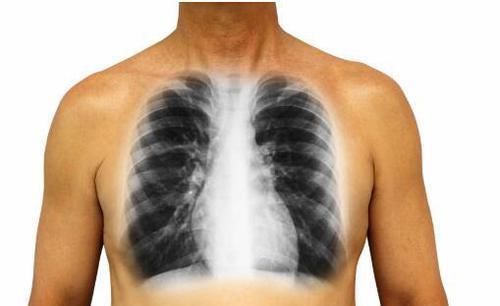

肺癌|肺癌到了晚期,4个变化很明显,骗不了人,别大意了

肺癌在刚患病的时候可能患者会感觉不疼不痒的,但是等到晚期的时候患者的症状就会变得多起来了,而且患者还会非常的痛苦。其实有很多人都不了解肺癌晚期的症状,到最后也没有采取有效的治疗措施,这样的话患者的痛苦会更严重的,所以接下来就给大家介绍一下肺癌晚期的表现。